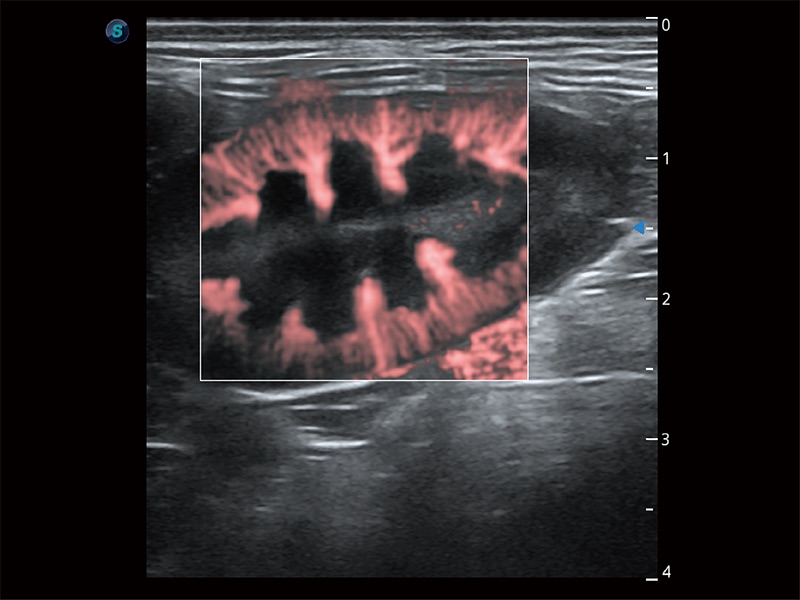

• Micro F 显微血流成像

极大提升超低速微细血流的检出能力,同时更精准地滤除软组织和超声信号,为兽用医生提供以往无法通过常规血流获得的疾病诊断信息。

(犬)肾脏显微血流